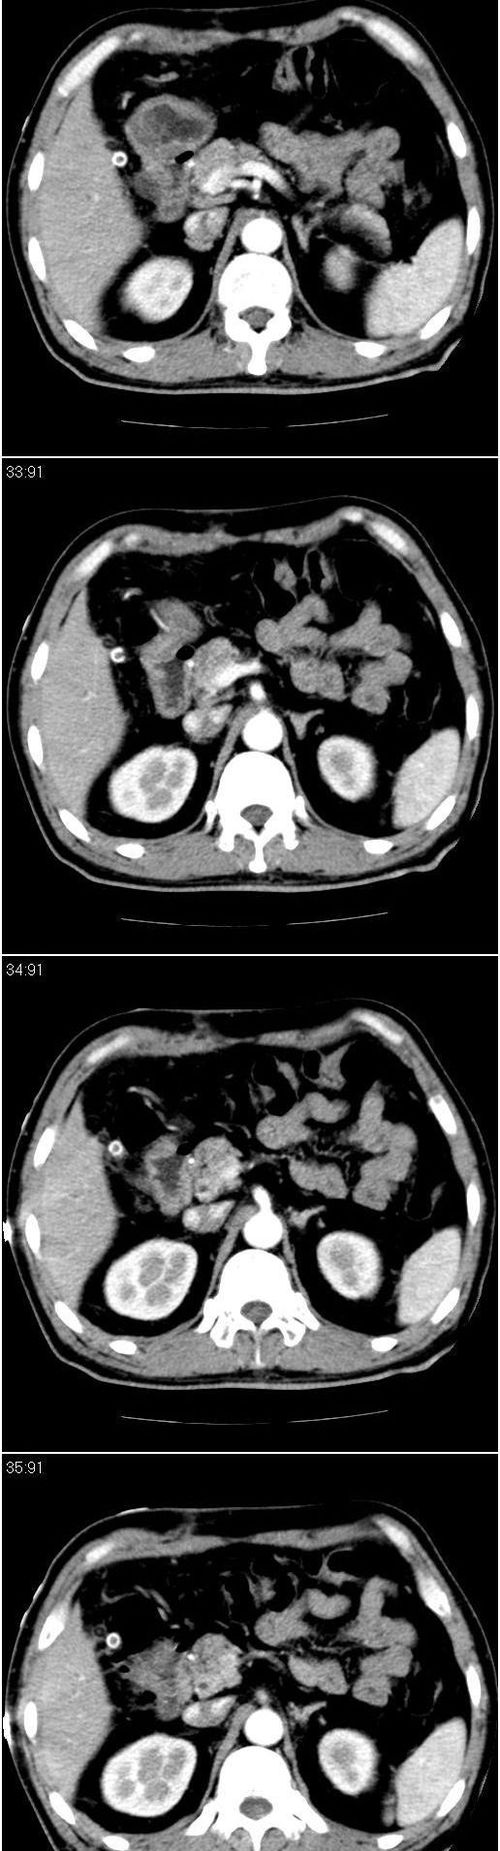

标题: CT13147:男,57岁。因胆结石阻塞性黄疸入院。 [打印本页]

标题: CT13147:男,57岁。因胆结石阻塞性黄疸入院。

男,57岁。因胆结石阻塞性黄疸入院。这是胆囊切除术后的照片,看看此片到底有什么问题。

肝内外胆管轻度扩张,胆囊窝内见引流管考虑胆囊切除术后改变.胃窦部软组织似增厚,建议胃镜检查.

支持 肝内外胆管轻度扩张,胆囊窝内见引流管考虑胆囊切除术后改变.胃窦部软组织似增厚,建议胃镜检查.